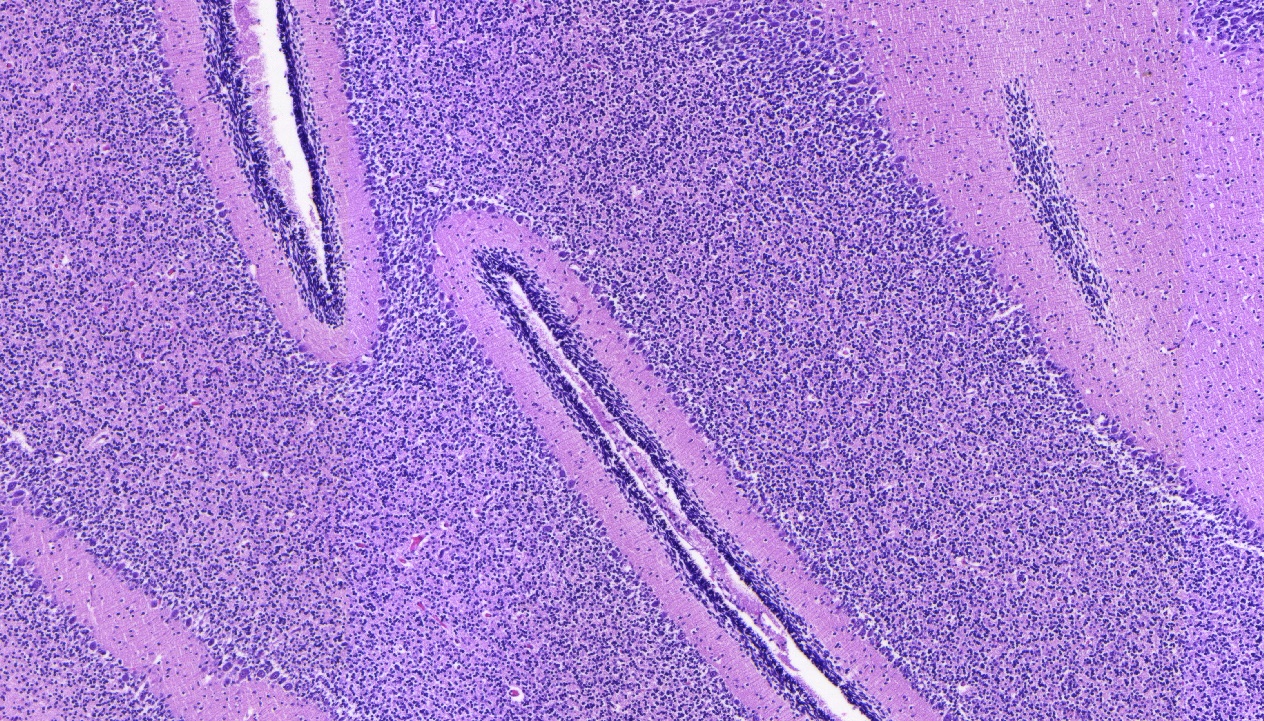

Les anatomopathologistes médicolégaux ont pour objectif de poser des diagnostics de maladies ou de lésions par analyse macroscopique puis microscopique, à partir de prélèvements tissulaires provenant de l’activité autopsique des instituts de médecine légale. Ils travaillent sur réquisition judiciaire.

Le champ d’action est vaste, allant d’une recherche de cause de la mort (ex : infarctus du myocarde, embolie pulmonaire, …) à la datation de lésion traumatique (ex : plaies, ecchymoses, …). Les constations microscopiques sont intégrées par le médecin légiste à l’ensemble du dossier afin de répondre aux questions posées par le magistrat.

Ces diagnostics s’appuient sur l’étude des modifications tissulaires et nécessitent la fabrication de blocs en paraffine et lames réalisés par une équipe de techniciens.